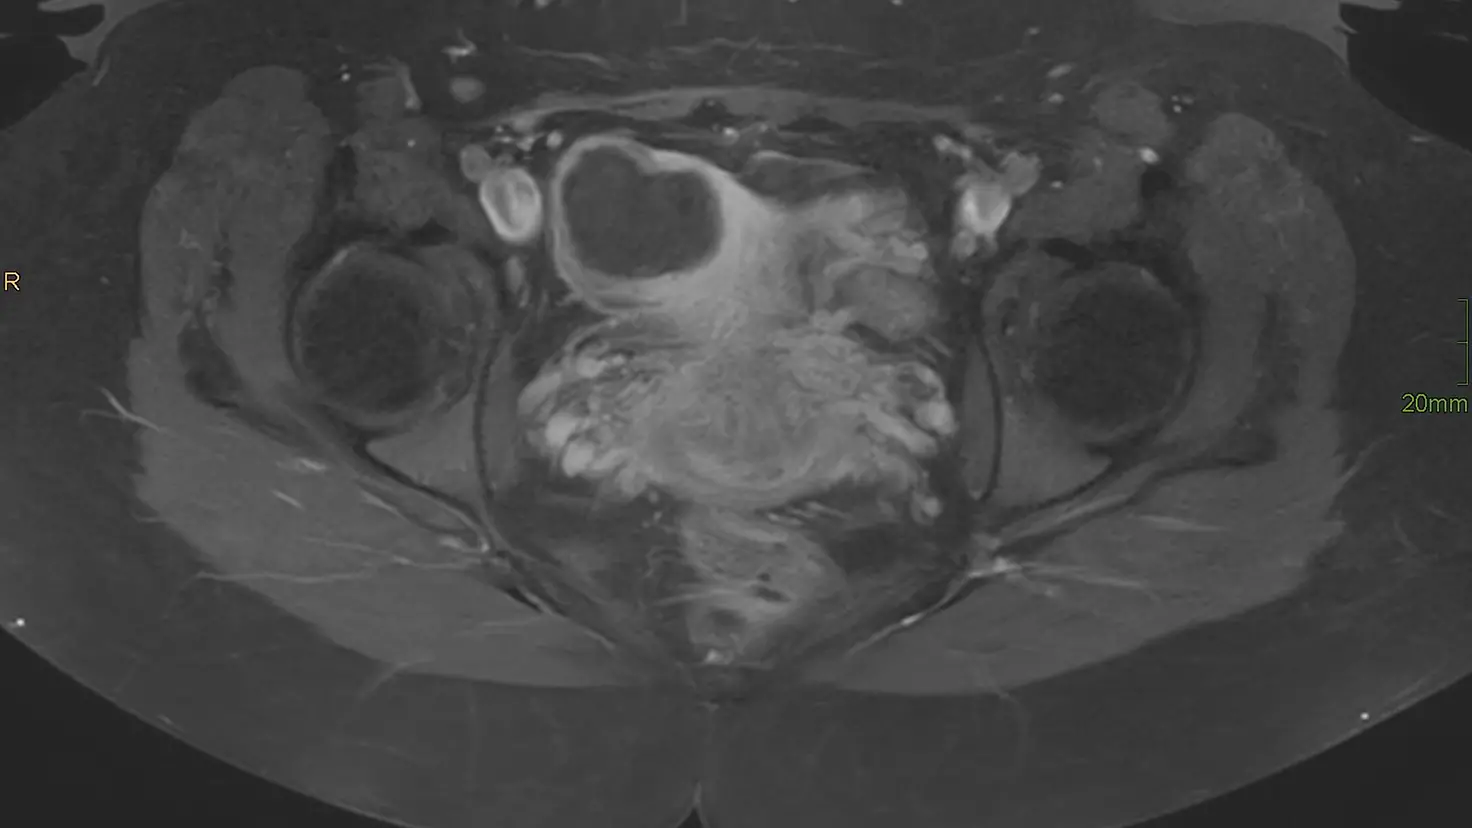

Vorbereitung einer Untersuchung im MRT

Das Foto darf im Rahmen der Berichterstattung über die Kooperation von Barmer und Marienhospital kostenfrei verwendet werden. Bitte geben Sie als Quelle „Philipps Healthcare“ an.

Als Bildunterschrift empfehlen wir: Zwei bis drei Stunden dauert die MR-HIFU Behandlung. Die Patientinnen können die Klinik schon kurz nach der Bestrahlung wieder verlassen.